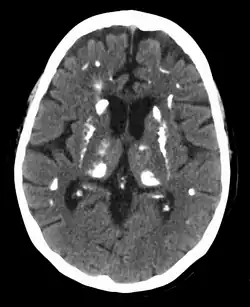

Calcification in the brain due to hyperparathyroidism

Hyperparathyroidism can cause hyperchloremia and increase renal bicarbonate loss, which may result in a normal anion gap metabolic acidosis.[32] ALP level can be elevated due to bone turnover. Additionally further tests can be completed to rule out other causes and complications of hyperparathyroidism including a 24-hour urinary calcium for familial hypocalciuric hypercalcemia, DEXA scan to evaluate for osteoporosis, osteopenia, or fragility fractures, and genetic testing.[33][34][35][36] Additionally a CT scan without contrast or renal ultrasound can be done to assess for nephrolithiasis and/or nephrocalcinosis if there is concern for it.[36]